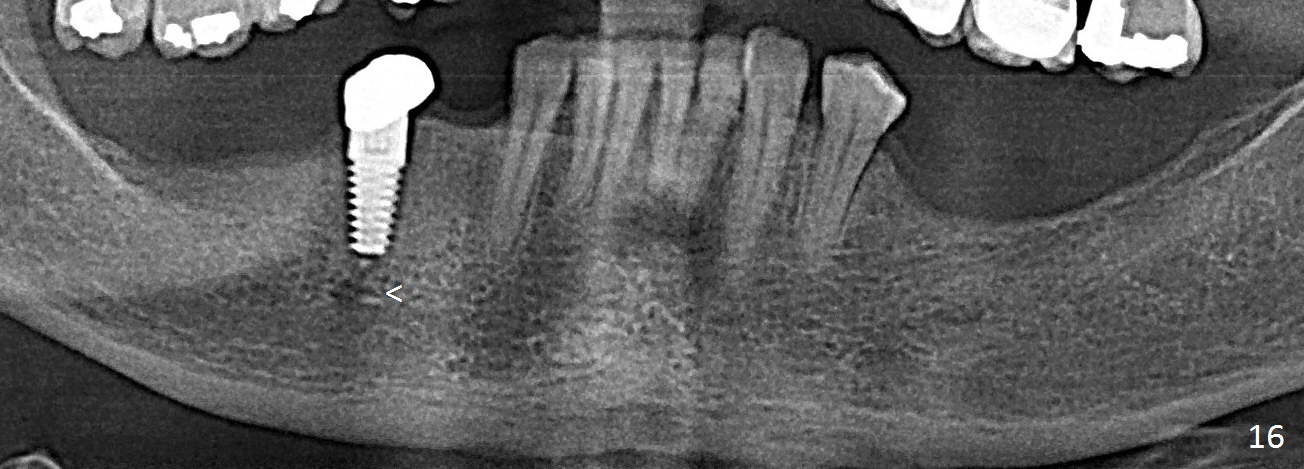

Panoramic X-ray taken 9 months post cementation shows the clearance from the Mental Loop (Fig.16). Although no drill technique is safe for the neurovascular bundle, the implant tends to deviate buccal, causing mental show through. It is still safe to make lingual osteotomy for a few millimeter and place a smaller implant (<4.5 mm). There is no bone loss 4 years 2 months post cementation (Fig.17) or 6 years 8 months post cementation (Fig.18).